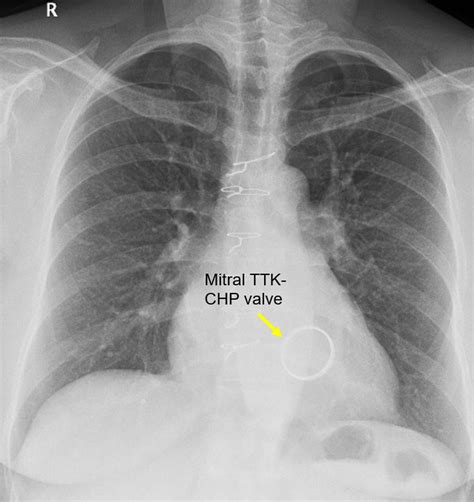

Pulmonary Thromboembolism - Undergraduate Diagnostic ...

Pulmonary Thromboembolism - Undergraduate Diagnostic ... from openpress.usask.ca

Presence of metallic objects within the area of examination. Posted by radiologypics ⋅ march 17, 2013 ⋅ leave a comment. Lateral ankle injury assessment online course: It is used to evaluate the lungs, heart and chest what are the limitations of chest radiography? In fact every radiologist and pulmonary physician should be an expert in chest film reading. Is there any inhaled foreign body? This imaging method can also check how a patient is responding to specific treatments. The interpretation of a chest film requires the understanding of basic principles. The interpretation of a chest film requires the understanding of basic principles. Living anatomy of the chest for 1st year medical students original version compiled by dr. Look for lung and pleural pathology. It first appears too complicated to read the chest xrays because we barely know what. ○ the right upper lobe.

Presence of metallic objects within the area of examination. Chest radiographs are the most common film taken in medicine. Look for lung and pleural pathology. Many clinical conditions can be evaluated by this simple radiology test. Posted by radiologypics ⋅ march 17, 2013 ⋅ leave a comment.